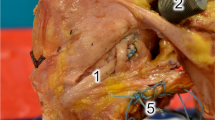

Anatomic SB ACL reconstruction was performed with the femoral and tibial tunnels placed within the marked ACL insertion sites on the femur and tibia, respectively [33]. Previously harvested porcine patellar tendon grafts, 8 mm in width and 15 mm in length, with single-side bone blocks were used for the reconstructions. The free ends of the folded grafts were whip-stitched using ultra-braided sutures with a tapered needle, and an extra-cortical button was added to the patellar bone block. One half of the graft width was coloured with a surgical pen to assess graft rotation during reconstruction (Fig. 1). For tunnel placement, a 2.4-mm guide wire was inserted into the centre of femoral ACL footprint. The femoral tunnel was drilled with a 7-mm cannulated femoral drill and then dilated with a 7.5-mm dilator through the accessory medial portal using the anteromedial portal to visualize of the femoral footprint (Fig. 2). A guide wire was inserted into the centre of tibial ACL footprint from the anteromedial aspect of tibia using a tibial drill guide system (Smith and Nephew Endoscopy, Andover, MA). The tibial ACL aimer angle was set to 55°, while the tibial tunnel was drilled with a 7-mm drill and then dilated with a 7.5-mm dilator after which point the graft was passed through the tibial tunnel [1, 14, 17, 23].

The bone block of the graft was compacted into the femoral tunnel with a compacter [1, 14, 23] (Fig. 3). In the non-rotated graft group, the tibial side of the graft was placed with the coloured side lying anteriorly, while in the rotated graft group the graft’s distal end was rotated externally (anatomic external fibre rotation) [8, 28] leaving the coloured side lying posteriorly with knee in 90° of knee flexion during arthroscopy (Fig. 4). Following graft placement, 20 flexion–extension movements were applied to the knees for pre-tensioning. The graft was tensioned at 60° of knee flexion (30° is full porcine extension) with a 40-N force applied by a ligament tension meter (Meira Corp., Nagoya, Aichi, Japan) [31]. The graft was fixed with an extra-cortical button on the femur and a screw/spiked washer on the tibia. A metallic interference screw was placed in parallel to the joint line to prevent graft rotation inside the tibial tunnel. For this study, IACUC/IRB approval was not required at the University of Pittsburgh, and all the porcine knees were acquired by a local butcher.